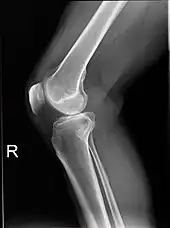

Right knee seen from the right side